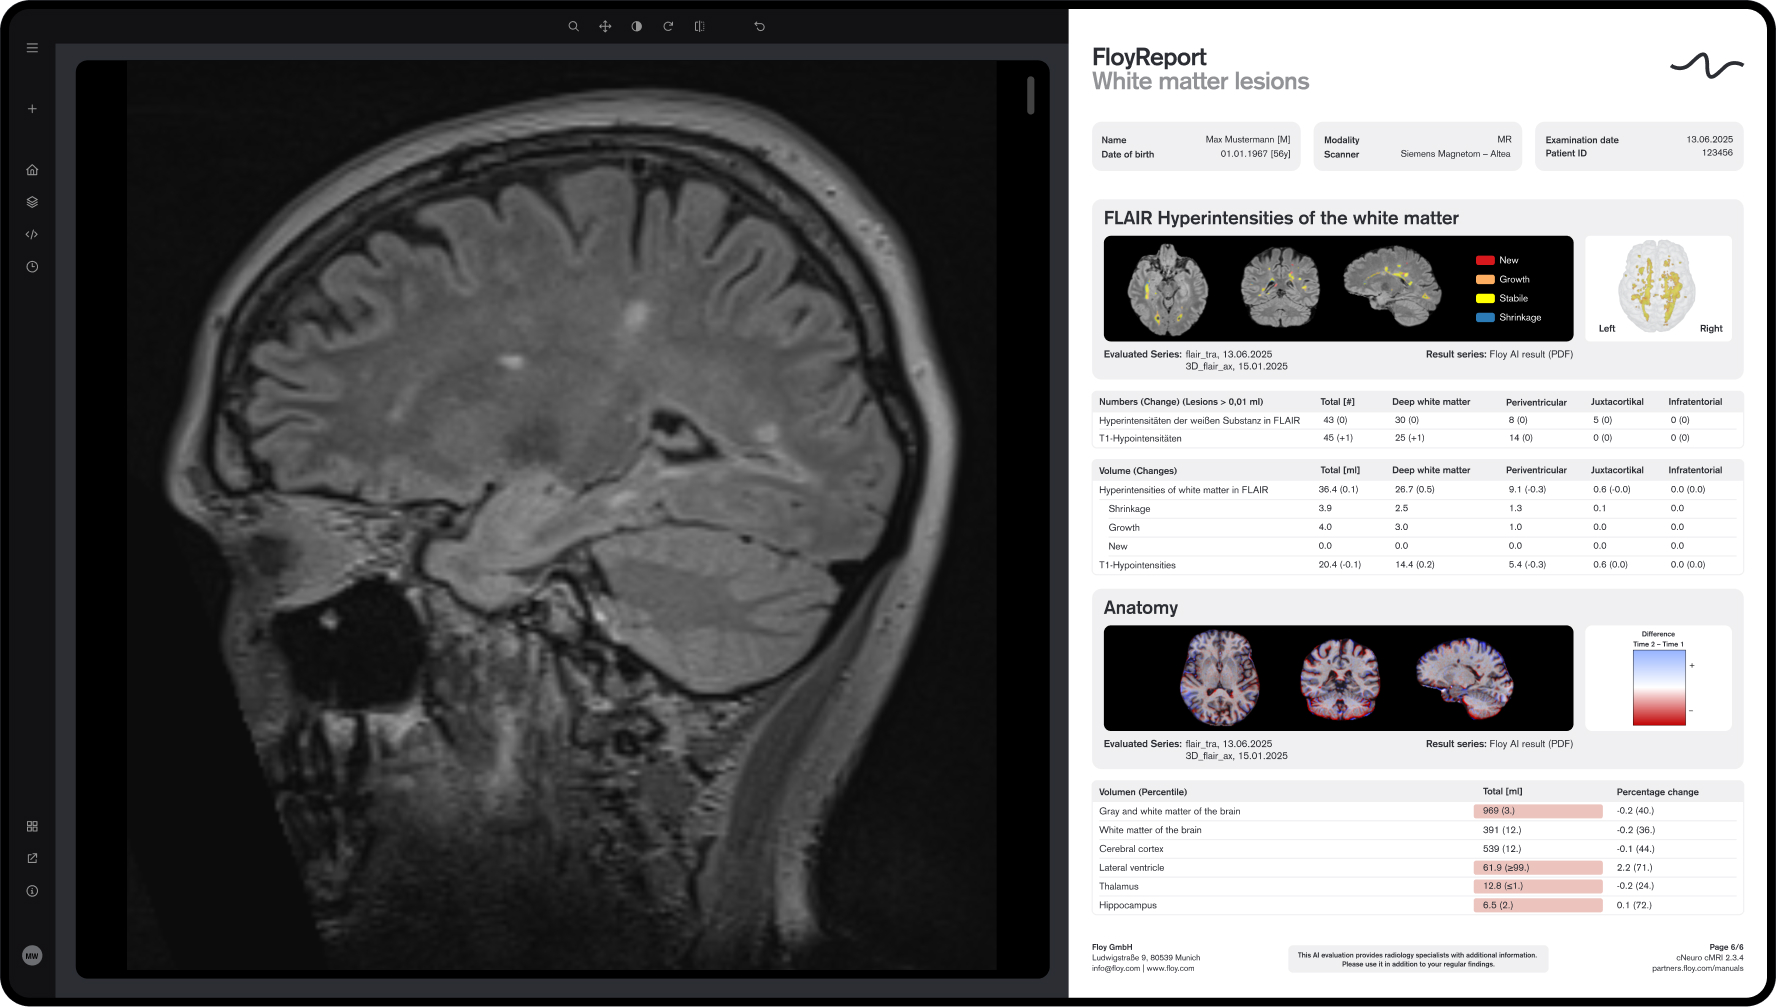

Floy® precisely and fully automatically measures brain region volumes in MRI, comparing them with age- and sex-specific normative cohorts to enable early diagnosis of neurodegenerative diseases such as various forms of dementia.

Floy® fully automatically detects and measures multiple sclerosis (MS) lesions in brain MRI, including comparison with prior scans, to support precise MS diagnosis.